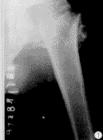

肱骨外髁骨折x片X線照片顯示肱骨小頭的骨折線多超過化骨核的1/2,或不通過小頭化骨核,而通過肱骨小頭與滑車間溝的軟骨在乾骺端處有一骨折線。骨折塊可向外側移位。骨折脫位型X線片,正位片顯示骨折塊連同尺橈骨可向橈側或尺側移位,側位片顯示可向後側移位,偶可見向前移位者。肱骨外髁骨折在X線片上表現為多種多樣,在同一骨折類型中表現也常不一。